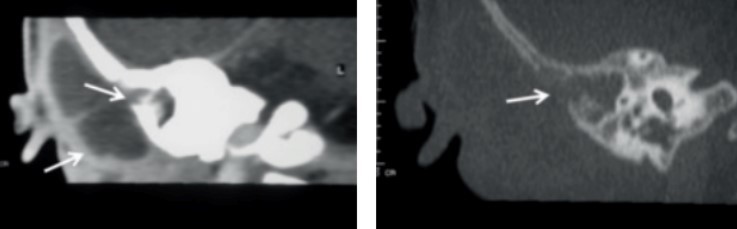

Voici le scanner injecté que vous faites réaliser

Question 7 : Quel est votre diagnostic ?

Les deux premières coupes sont des coupes frontales ou coronales ; la première en fenêtre parenchymateuse avec visualisation d’un abcès cloisonné sous-périosté, la deuxième en fenêtre osseuse avec lyse osseuse (c’est ce qui signe la mastoïdite, un comblement simple mastoïdien est présent dans les TOUTES LES OMA). Les deux dernières coupes sont des coupes axiales, l’une en parenchymateux, l’autre en fenêtre osseuse.

On voit ici sur la flèche de droite la thrombose du sinus latéral.

C’est donc une mastoïdite aiguë compliquée car s’y associe la thrombose.

L’abcès est bien ici sous-périosté à l’extérieur et au contact de l’os. Un abcès intra-parenchymateux serait en cocarde et dans la substance blanche cérébrale.